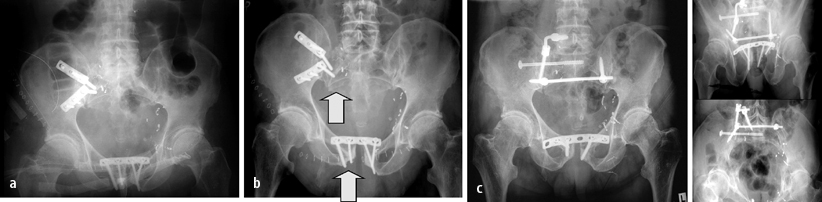

Ein valider Beleg der erreichten Behandlungsqualität (z. B. intraoperative Reposition, korrekte Implantatlage) ist nicht allein wegen potenzieller späterer juristischer Implikationen, sondern v. a. zur Sicherung des klinisch-wissenschaftlichen Zusammenhangs zwischen Repositionsresultat und Outcome relevant. Zwar wird die Wertigkeit einer postoperativen CT-Kontrolle noch kontrovers diskutiert [13], nicht zuletzt weil der bisherige Goldstandard der postoperativen Bildgebung die Standardröntgenuntersuchung darstellt [4, 6] und biologische Parameter der jeweiligen Verletzung und Versorgung hiermit nicht detektiert werden können, doch gibt diese Form der postoperativen Bilddokumentation dem Operateur ein gutes Instrument an die Hand, residuale Fehlstellungen nach Rekonstruktion und die adäquate und gesichert extraartikuläre Implantatlage zu dokumentieren, somit „Schwachstellen“ der spezifischen Versorgung nachzuweisen (Abb. 8 c,d). Hieraus kann neben einem persönlichen Lerneffekt auch eine Indikation für eine operative Frührevision abgeleitet werden. Moderne Formen der intraoperativen Bildgebung (z. B. 3D-Bildverstärker, Abb. 8 c) sind hierbei von Vorteil, da bei mittlerweile guter Abbildungsqualität und limitiertem Zeitaufwand dem Operateur die Chance geboten wird, ggf. intraoperativ weitere Nachkorrekturen vorzunehmen, also die postoperative CT-Untersuchung und einen evtl. Zweiteingriff entbehrlich zu machen. Der Vergleich zwischen der intraoperativen 3D-Bildverstärkung und einem postoperativen Standard-CT mit multiplanerer Rekonstruktion scheint dies zu untermauern (Abb. 8 d–f).

Fall 7, 52-jähriger Polytraumapatient (AO 62A2.3), a,b erhebliche Impressionszonen und osteochondrale Frakturen im Pfannendachbereich, c intraoperative Kontrolle von Reposition und Implantatlage nach ORIF mit 3D-Bildverstärker, d Entfernung der markierten Zugschraube und nochmalige 3D-Bildverstärker-Kontrolle, e,f postoperatives a.-p. Röntgenbild und 2D-Rekonstruktion nach CT, weitere Erläuterungen s. Kasuistik

Fall 7

Der 52-jährige männliche Polytraumapatient (AO 62A2.3) wies erhebliche Impressionszonen und osteochondrale Frakturen im Pfannendachbereich auf.

Nach ORIF über einen erweiterten dorsalen Zugang mit Trochanter-Flip-Osteotomie wurden die Reposition und die Implantatlage intraoperativ mit dem 3D-Bildverstärker kontrolliert. Die dabei identifizierte „Schwachstelle“ der operativen Versorgung wurde in gleicher Sitzung behoben und das Ergebnis erneut intraoperativ kontrolliert.

Die postoperative Röntgenuntersuchung und CT-Rekonstruktion bestätigten den Befund der intraoperativen Kontrollaufnahme (Abb. 8).